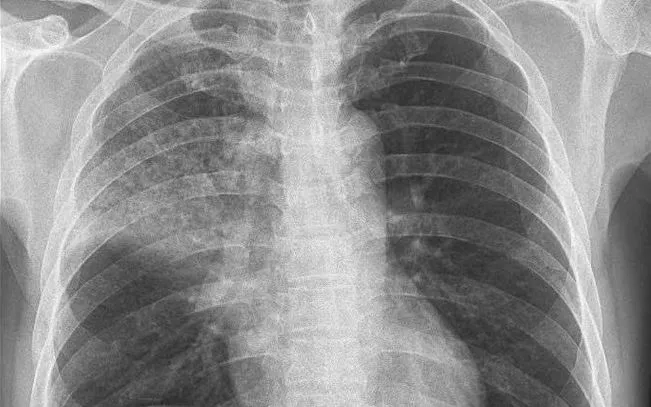

Sau 7 ngày điều trị, tình trạng bệnh nhân cải thiện rõ rệt: hết sốt, giảm ho, giảm đau ngực, ăn uống, ngủ nghỉ tốt, các chỉ số sinh tồn ổn định, X-quang phổi cho thấy vùng viêm mờ đã thu nhỏ đáng kể.